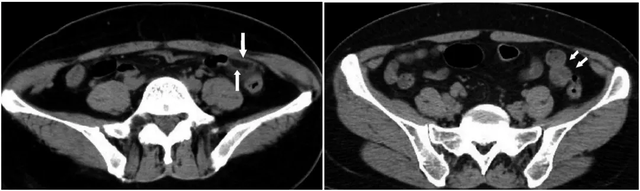

图身体①病例有啥:患者,男性,50岁,CT轴位示回盲部多发憩室(三角箭),邻近肠壁增厚,憩室周围脂肪密度增高、筋膜增厚(长箭),手术病理证实为急性原因阑尾炎合并回盲部多发憩室炎。

图②病例:患者,男性,63岁。②a:CT轴位示乙状结肠多发憩室(三角箭);②b:CT冠状位重组示乙状结肠系膜侧憩室(三角箭),周围脂肪密度增高女人(长箭),憩室周围积气(短箭)。